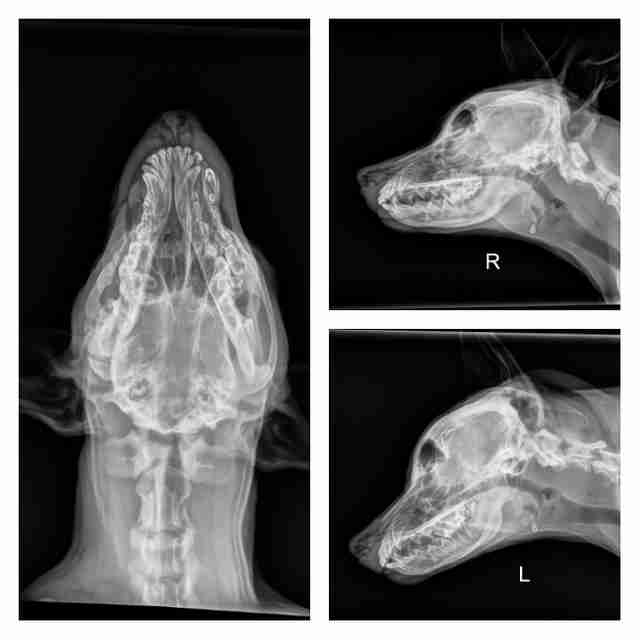

Com apenas quatro meses de idade, ele tinha um forte inchaço além de deformidades no lado direito de sua cabeça e do maxilar. Isso o deixava com a aparência meio ”esmagada”. O cachorro mal conseguia abrir a boca ou mesmo deixar a língua entre os dentes. De qualquer forma, ele não desistia de tentar dar beijos em todos.

Segundo o veterinário, ele estava com uma séria infecção que poderia ter sido gerada a partir de uma mordida de algum animal. Assim, o médico prescreveu antibióticos e remédios para a dor e o deixou internado sob cuidados médicos. Porém, conforme seu corpo ia crescendo, seu rosto foi ficando cada vez mais amassado e sua habilidade de abrir a mandíbula diminuiu. Sem falar em todo o peso que ele perdeu.

E foi aí que descobriram: Squish tinha fraturas significantes em seu crânio e em sua mandíbula. E mesmo que tudo estivesse normal com seu olho direito, ele estava afundado atrás dos ossos triturados que davam suporte ao olho. Sem falar que ele tinha uma enorme quantidade de tecido cicatricial em torno de sua mandíbula. Era esse tecido que impedia que seu maxilar crescesse conforme seu corpo. Ou seja, cada vez era mais e mais difícil abrir a boca.

Segundo os veterinários, Squish foi atacado por alguém que usou um objeto para feri-lo. Logo, ele teria que passar por um longo tratamento, mas era incerto se seu problema ia ou não ser resolvido. Mas a grande questão ainda era: quem iria querer adotá-lo sabendo de todos os custos para curá-lo?

Assim, não restava outra opção para Danielle a não ser conseguir sua cura. Foram vários tratamentos e cirurgias, mas ela não desistiu dele. Rapidamente, o Dr. Heldmann teve que remover parte de seu maxilar inferior e o tecido cicatricial que o impedia de abrir a boca. Quando a cirurgia acabou, Squish não conseguia se conter. Ele agora conseguia abrir a boca.